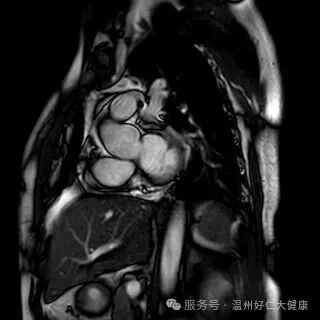

针对心脑血管早筛的核心需求,我院全力推进冠脉磁共振检查技术普及,凭借无创、无辐射、不打造影剂的硬核优势,攻克传统筛查的痛点,成为不同人群冠脉血管筛查的优选方案,让早期血管病变无所遁形:无创安全,适配全人群:全程无需插管、不注射造影剂,从根源规避造影剂过敏、肾脏代谢负担等问题,肾功能不全、备孕、造影剂过敏等特殊人群也能安心检查,真正实现 “零负担筛查”; 零辐射高精准,捕捉隐匿病变,无任何电离辐射,即使多次复查也不会对身体造成损伤;成像精度可清晰识别冠脉血管软斑、硬斑等斑块性质,精准判断血管狭窄程度,哪怕是早期隐匿的微小病变,也能精准检出; 一站式筛查,兼顾血管与心脏:不仅能排查冠脉血管病变,还能同步评估心肌灌注、心脏收缩舒张功能,清晰呈现心肌细微结构,一站式完成 “血管 + 心脏” 全面检查,为冠心病早期筛查、高危人群动态监测提供精准的诊断依据。